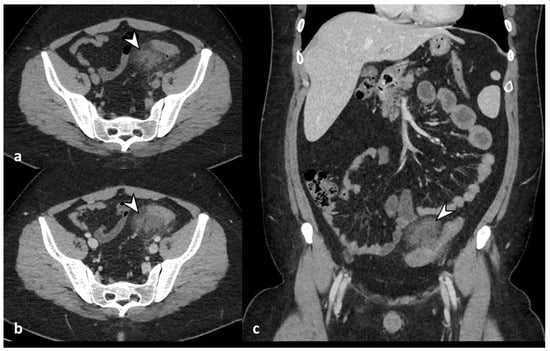

Figure 3. Axial unenhanced (a), axial and coronal contrast-enhanced CT images (b,c) show wall thickening of the left colon and inflammatory mass, without walls, located near the inflamed colonic tract, oval in shape, without an enhancing wall, that represents a peridiverticular phlegmon (arrowheads).